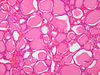

1

Q

A

Liver